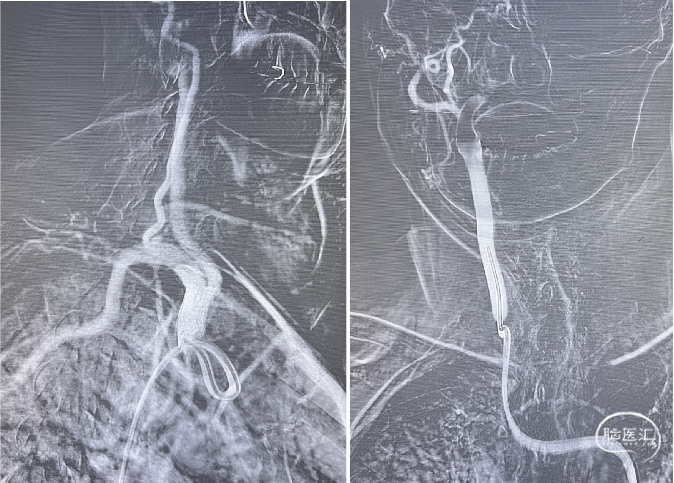

脑血管造影:3型主动脉弓,右侧颈内动脉起始段闭塞,后循环及左侧颈内动脉均未向左侧颈内动脉供血区代偿。

3型主动脉弓,用Mani管超选至右颈总动脉,用260cm加硬泥鳅导丝交换出,在泥鳅导丝导引下,用125cm的多功能管将6F Infinity长鞘置于右颈总动脉,提供稳定支撑。

Infinity 长鞘 提供稳定支撑